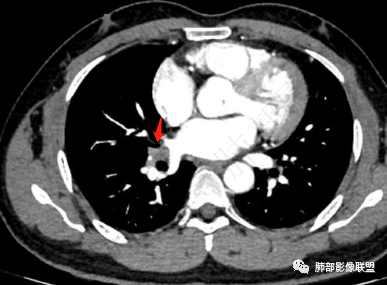

2、胸部CT右肺下叶胸膜下肿块性病变,边缘可见分叶毛刺、边缘膨隆,似有指状凸起,邻近胸膜稍牵拉凹陷,叶间裂以为不明显,提示收缩力较弱。近端支气管进入后截断,病灶内密度尚均匀,增强后可见轻度强化,未见空洞或钙化,并可见血管影进入。右侧肺门及纵隔内可见肿大淋巴结影。无胸腔积液。

3、综合患者临床症状及影像表现,需要考虑肿瘤性病变和非肿瘤性病变,肿瘤性病变需要考虑普通浸润性腺癌或结节型粘液腺癌、淋巴瘤、淋巴上皮瘤样癌、小细胞肺癌等,非肿瘤性病变主要考虑肺脑同病中的隐球菌。①普通浸润性腺癌,以肺外周多年、混合磨玻璃或实性结节/肿块,多见分叶、毛刺、胸膜凹陷、血管集束等征象,本例收缩力较弱、且强化偏轻,不够典型。②粘液腺癌,腺癌的特殊类型。多位于胸膜下(90%位于胸膜下,70%位于下叶胸膜下),边缘清或不清的GGO:提示粘液外渗,少数为纯GGO,缺乏中心纤维化区:毛刺、胸膜凹陷征少,很少胸膜侵犯,淋巴结转移少见,增强后无强化或低强化,本例病灶位于胸膜下,强化轻,收缩力弱,结节期粘液腺癌确实可以符合。③小细胞肺癌,吸烟男性多见,典型征象包括娘小崽大、腊肠样凸起、冰冻纵膈等,本例胸膜下病变大、但肺门淋巴结肿大程度较轻,不符合常见小细胞癌生物学行为,但有可疑指状凸起,小细胞肺癌不能完全除外。④淋巴上皮瘤样癌,少见的恶性肿瘤,患病年龄较轻,肿瘤多位于胸膜下,边缘多光滑,病灶周围可见磨玻璃,毛刺及分叶、胸膜凹陷少见,近端支气管可截断,增强多为中度-明显强化,本例除了强化程度偏轻外,影像表现基本可符合。⑤淋巴瘤,原发肺内淋巴瘤较少见,病灶多位于支气管血管束周围或胸膜下,密度多较均匀,边缘可膨隆也可平直收缩,可见支气管充气征、血管造影征等,强化多为轻中度,本例肺内结节血管穿行自然,局部有血管漂浮,长轴与支气管走行基本一致,肺门淋巴结肿大,不能排除。⑥隐球菌,影像表现可分为孤立结节型、大片实变型、多发结节或实变型、弥漫型。病变多位于胸膜下,边缘平直为主、可伴晕征,可见支气管穿行、部分可见支气管截断,密度多较均匀,部分可伴空洞,增强多为轻中度强化、延迟强化。本例病变位于胸膜下,收缩力弱,强化程度轻,但没有呼吸道症状,病变近端支气管截断,肺门淋巴结大,这些征象都难以用隐球菌解释,基本排除。